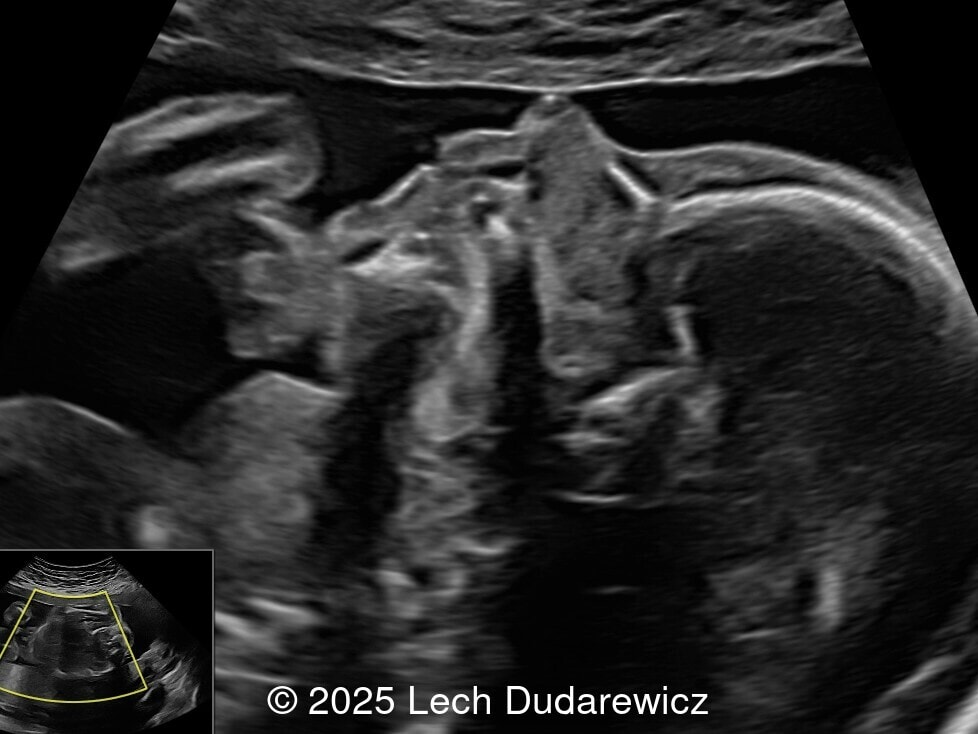

A 33-year-old nullipara with non-contributory medical history presented at 20 weeks, 6 days based on an early scan. Ultrasound revealed the following findings. There were no other apparent abnormalities. What is the most probable diagnosis?

Image 1

We present a case of fetal hypothyroidism diagnosed at mid-trimester ultrasound.

Ultrasound images demonstrated a symmetrically enlarged thyroid gland that was isoechoic to slightly hyperechoic relative to the surrounding tissues. Color Doppler revealed peripheral hypervascularization of the thyroid, known as the “peripheral vascular rim sign”. No internal parenchymal hyperperfusion was noted. Amniotic fluid volume was within normal limits and no structural anomalies were observed in the remainder of the scan.

Prenatal ultrasound is the preferred method of screening for head and neck masses. The first ultrasound diagnosis of a fetal goiter was made by Weiner et al. in 1980 [11], and since then several cases have been published, mostly isolated or small series [12,13]. Ultrasound can accurately assess the size, location, internal blood supply, and growth of the fetal goiter, as well as evaluating its effects on neighboring structures and amniotic fluid volume. Key sonographic findings include a homogeneous, echogenic, symmetric mass in the anterior portion of the fetal neck corresponding to the thyroid enlargement (measurements above the 95th percentile for gestational age), polyhydramnios (not always present), and abnormal fetal neck contour [1]. On color Doppler evaluation, peripheral hyperperfusion ("peripheral vascular rim sign") supports the diagnosis of hypothyroidism with a hypertrophic but inactive thyroid gland. Diffuse parenchymal hyperperfusion (“thyroid inferno”), due to an overactive thyroid gland, is expected in hyperthyroidism [14,15]. Three-dimensional ultrasound may facilitate the parent’s understanding of the fetal goiter [16] and magnetic resonance imaging (MRI) can be useful for evaluating the compression and patency of the trachea and esophagus [17].